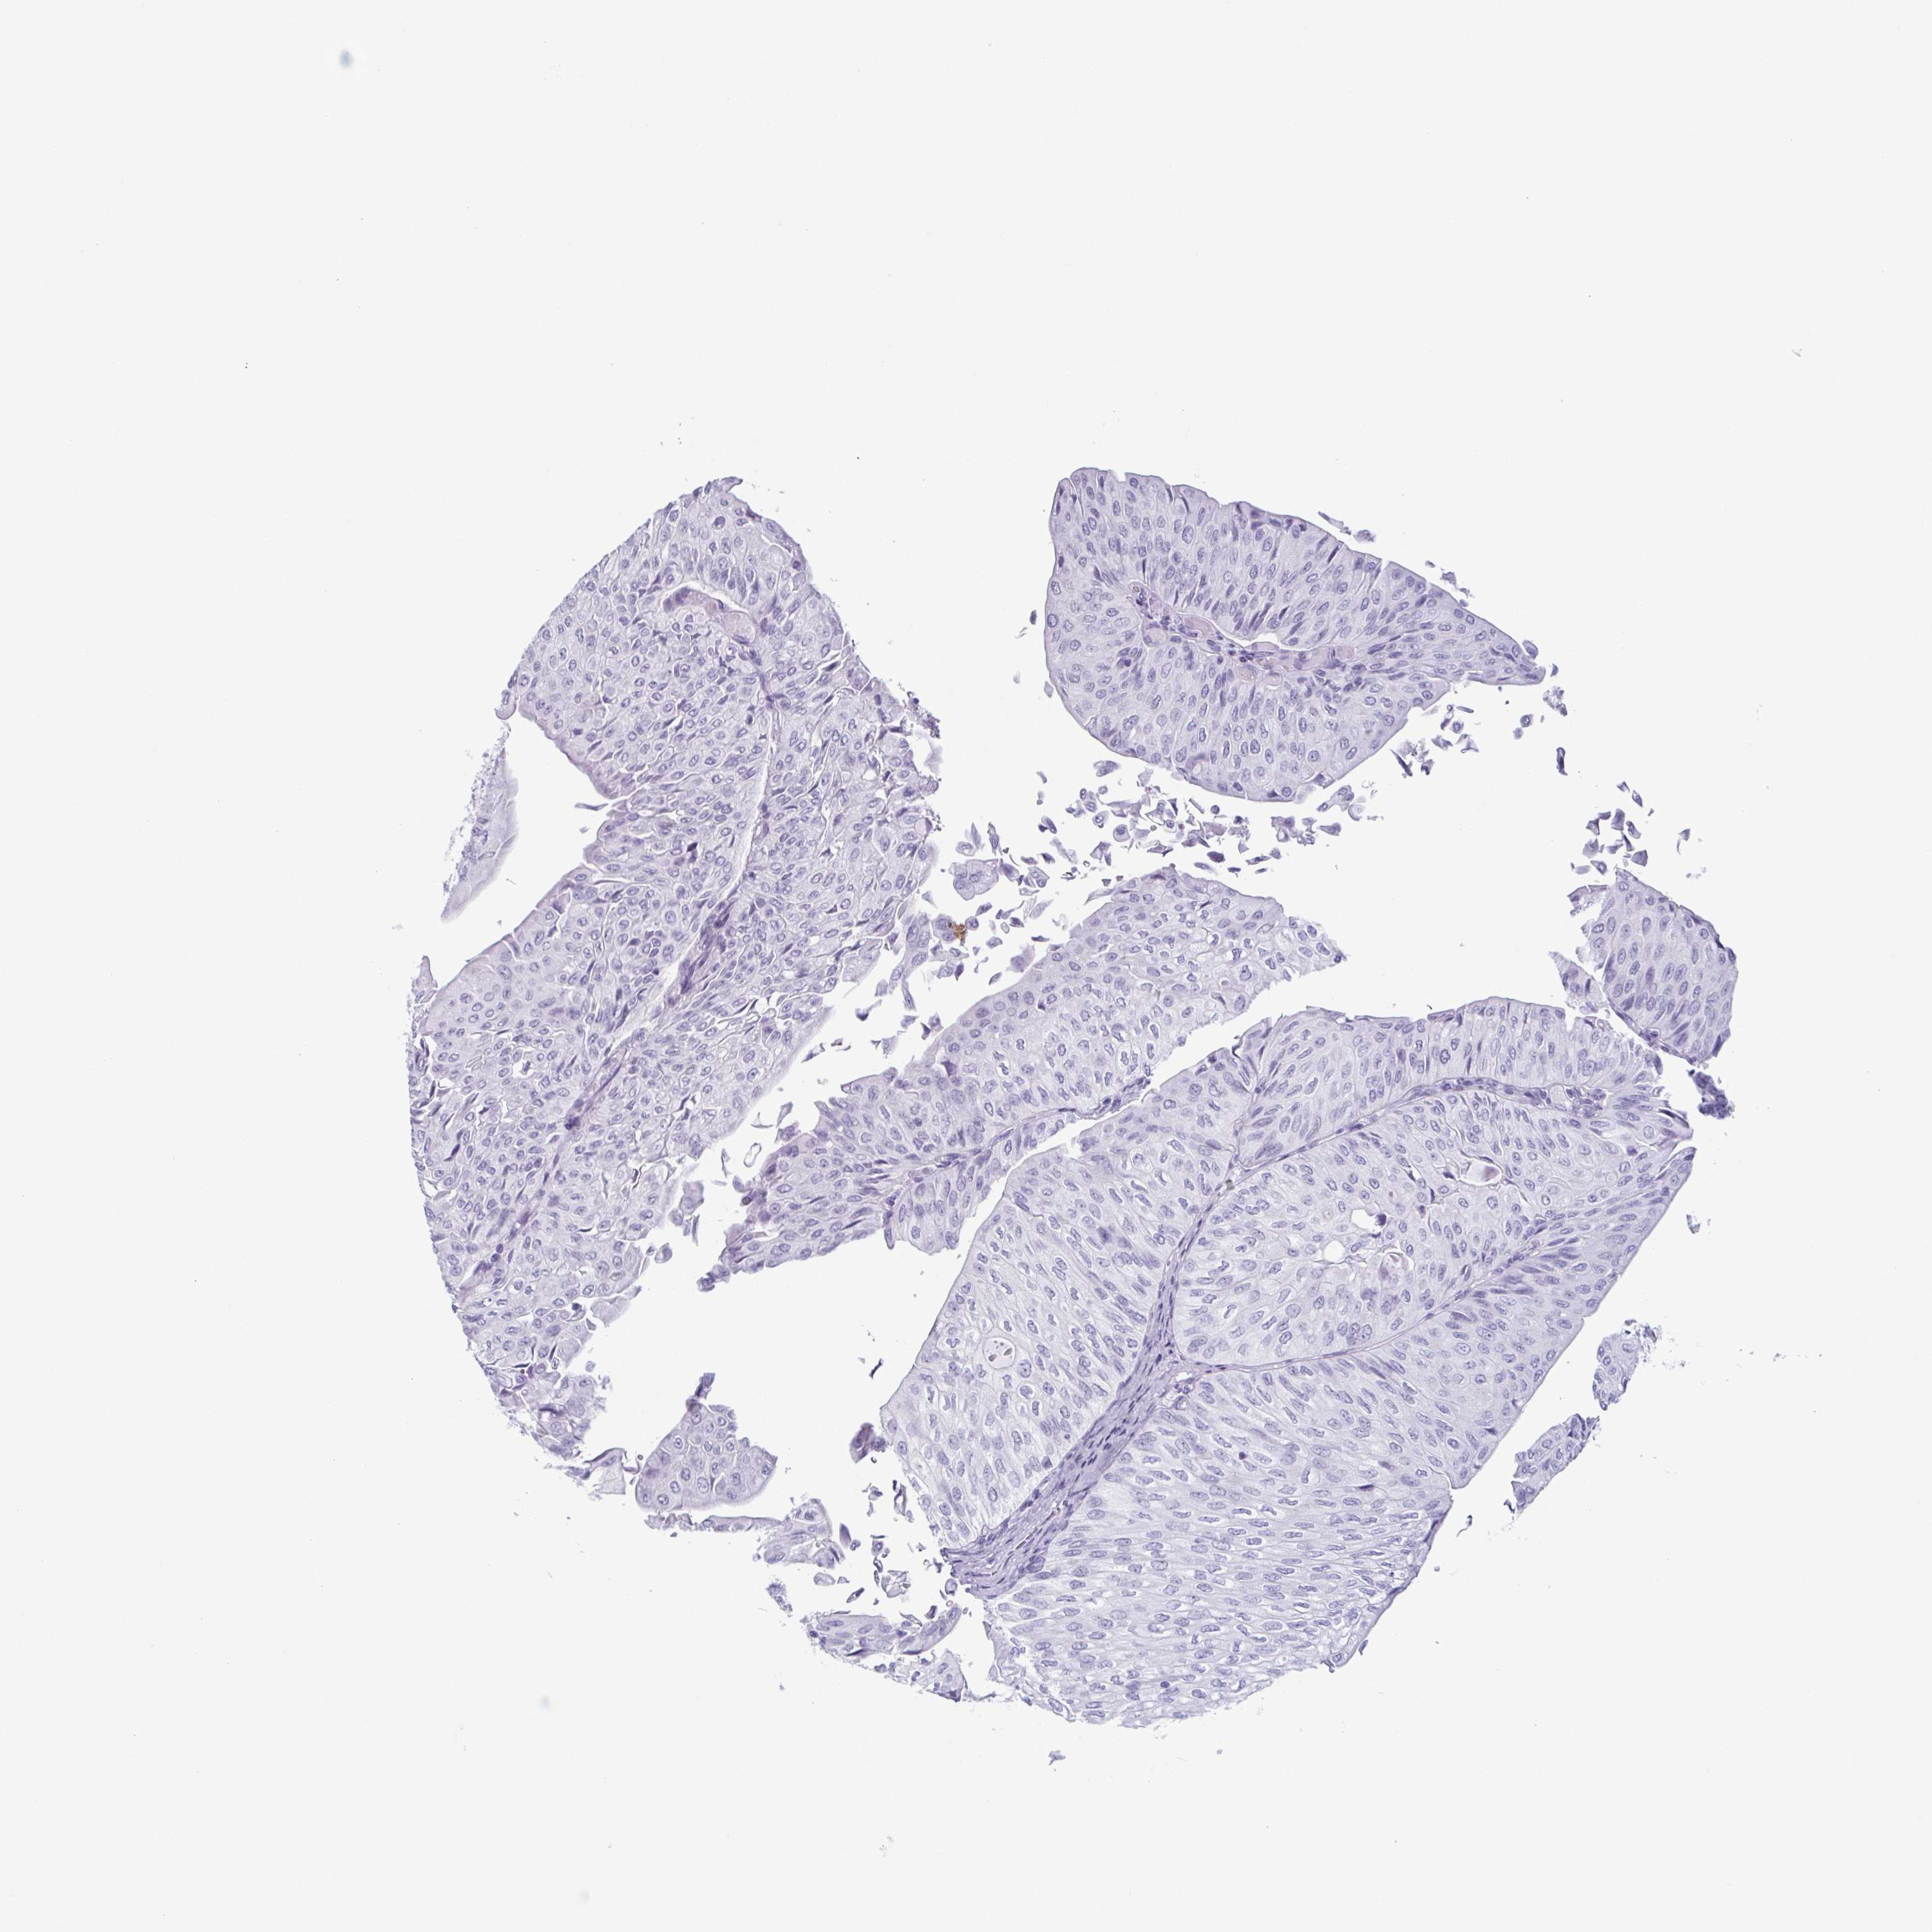

UROTHELIAL CANCER - Protein expressioni

A mouse-over function shows sample information and annotation data. Click on an image to view it in a full screen mode. Samples can be filtered based on level of antibody staining by selecting one or several of the following categories: high, medium, low and not detected. The assay and annotation is described here.

Note that samples used for immunohistochemistry by the Human Protein Atlas do not correspond to samples in the TCGA dataset.

Antibody stainingi

Antibody staining in the annotated cell types in the current human tissue is reported as not detected, low, medium, or high, based on conventional immunohistochemistry profiling in selected tissues. This score is based on the combination of the staining intensity and fraction of stained cells.

Each image is clickable and will lead to virtual microscopy that enables deeper exploration of all samples and also displays staining intensity scores, fraction scores and subcellular localization as well as patient and tissue information for each sample.

Antibody HPA037593

Antibody HPA037594

Antibody HPA061503

Staining

High

Medium

Low

Not detected

Intensity

Strong

Moderate

Weak

Negative

Quantity

>75%

75%-25%

<25%

None

Location

Nuclear

Cytoplasmic/membranous

Cytoplasmic/membranous,nuclear

Urothelial carcinoma, High grade

Urothelial carcinoma, NOS

Urothelial carcinoma, Low grade